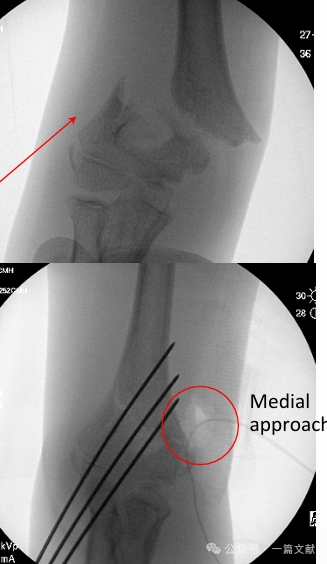

II. Imaging Studies: Plain radiographs are usually sufficient. AP and lateral views of the elbow are required. Obtain ipsilateral forearm/wrist radiographs to assess for associated injuries. Evaluate for the posterior fat pad sign in nondisplaced fractures (indicated by arrow).

Open Reduction Technique:

* Approach Selection Principle: Follow the metaphyseal ridge.

* Anterior Approach: Indicated for posterior displacement, or when vascular injury and/or median nerve injury are present.

* Medial Approach: Indicated for posterolateral displacement or flexion-type injuries.

* Lateral Approach: Indicated for posteromedial displacement.

* As shown in the figure: For a fracture with posterolateral displacement, a medial approach was used for open reduction.